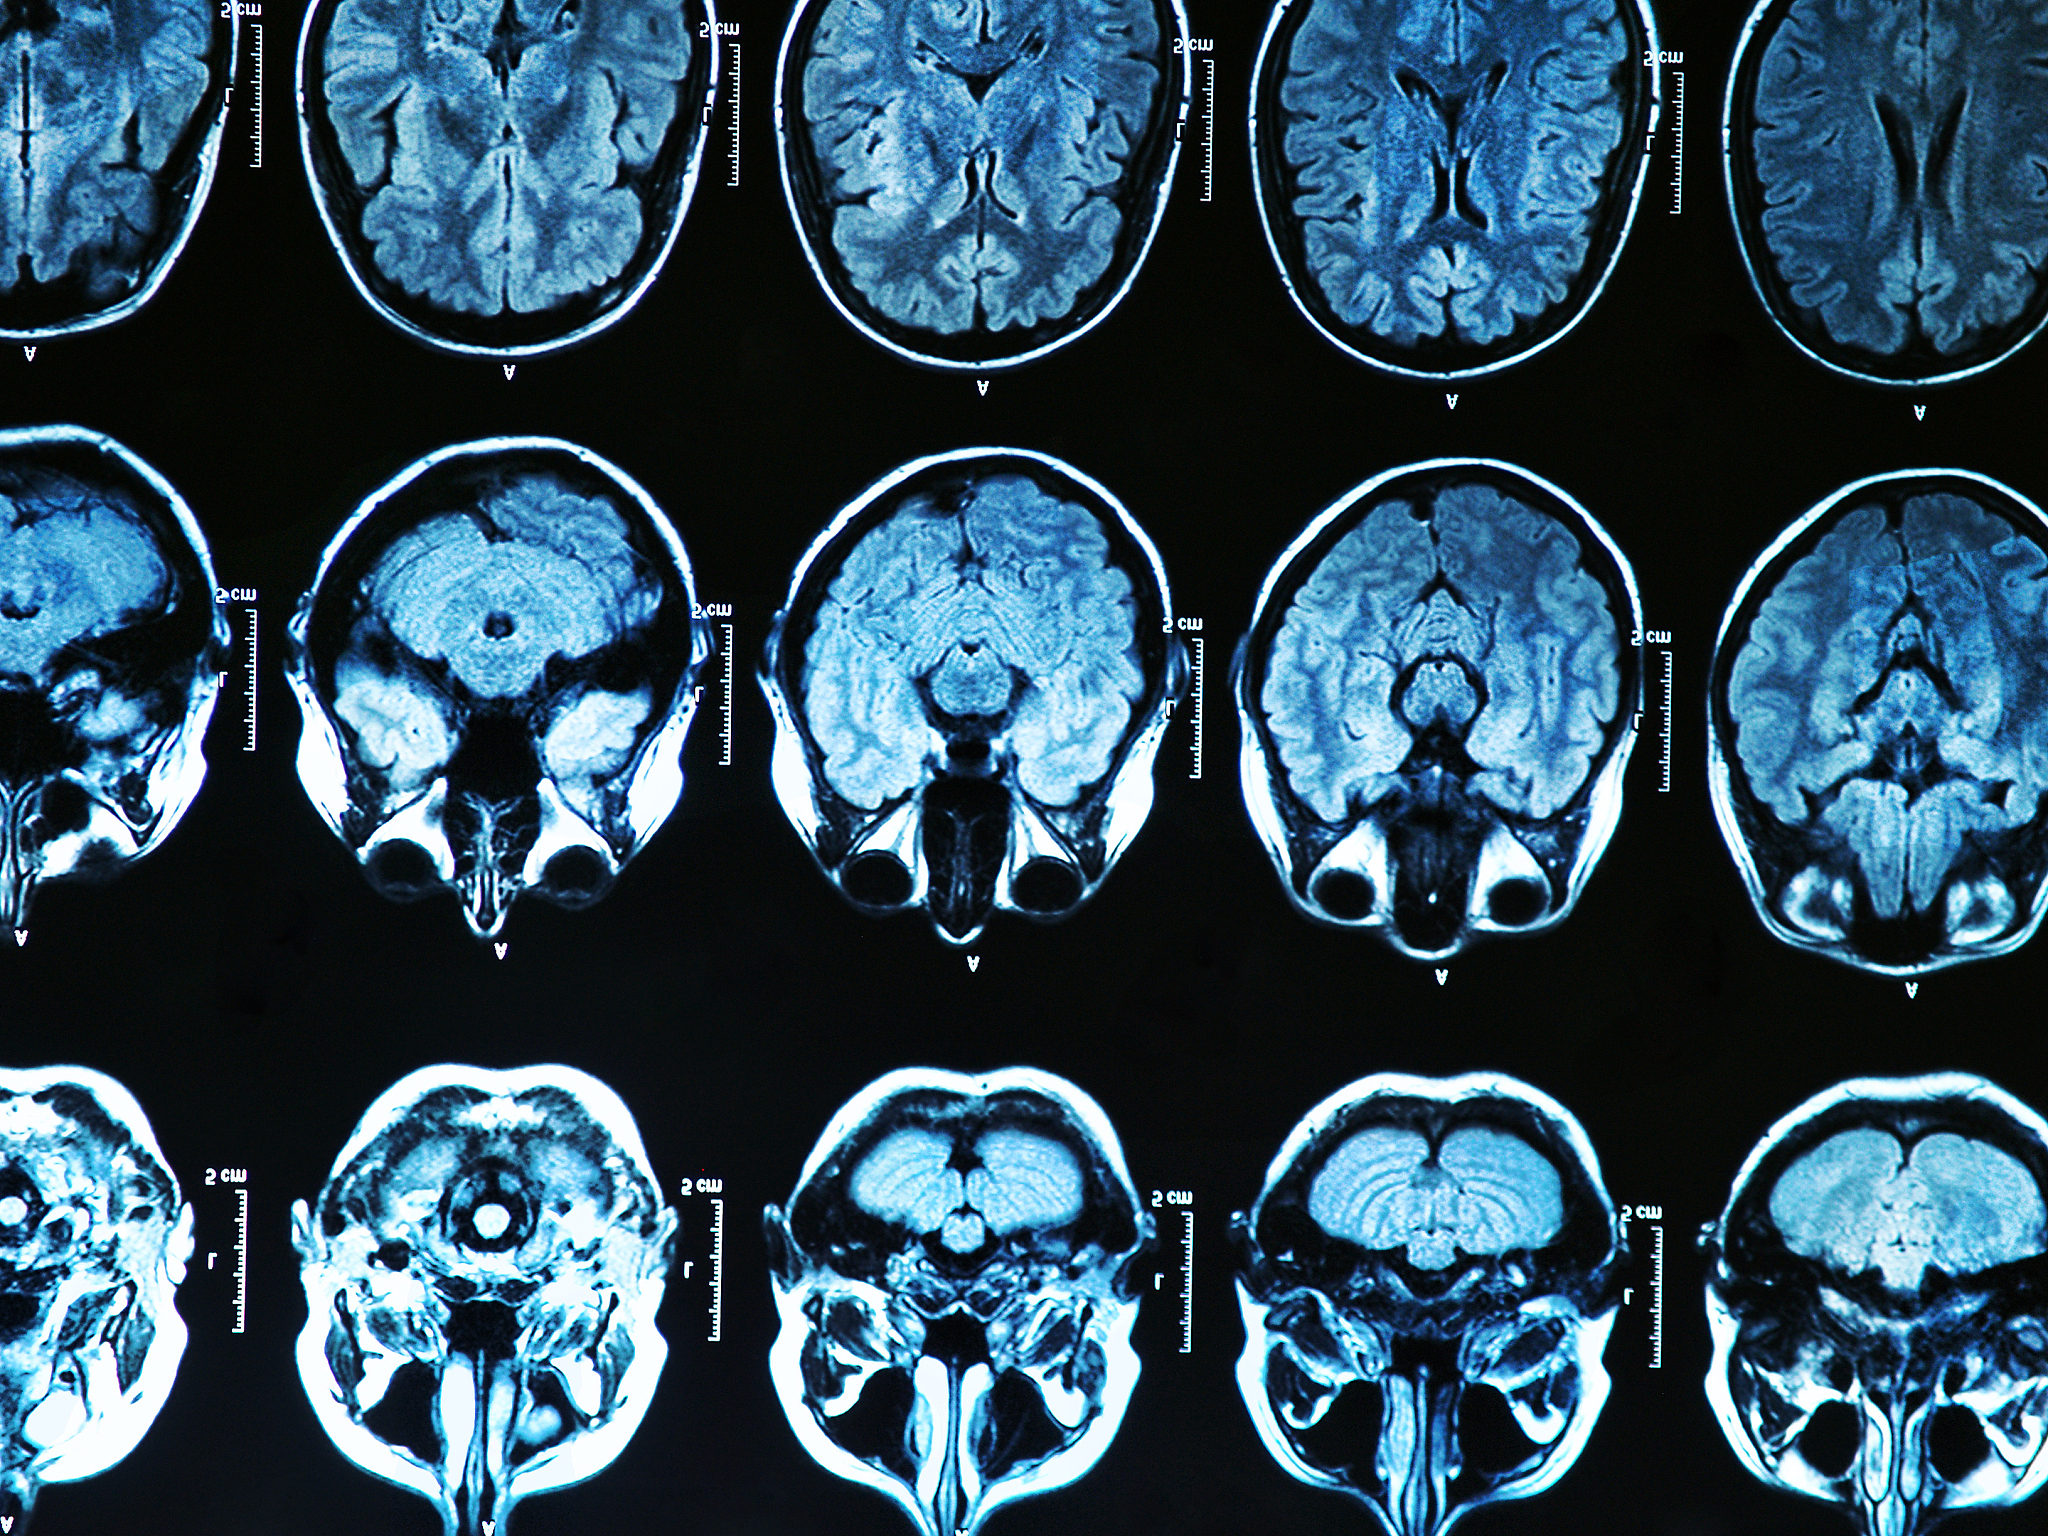

颈动脉斑块新生血管评估:增强CT和增强MRI的有效性

Both enhanced CT and enhanced MRI can effectively evaluate neovascularization within carotid artery plaques. 增强CT和增强MRI都能很好地评价颈动脉斑块内新生血管。